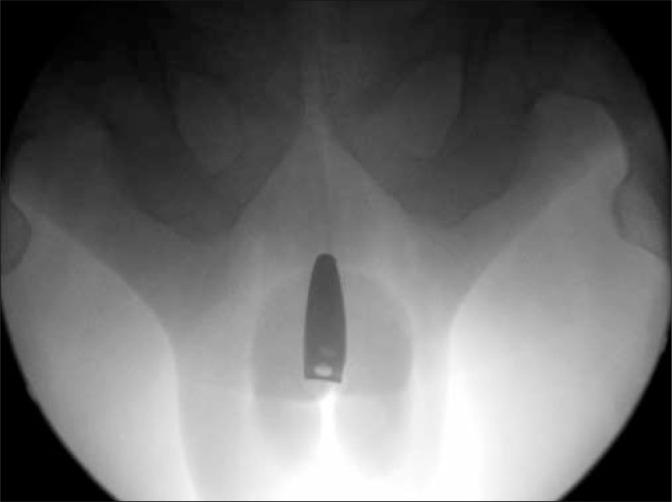

A 37-year-old mentally retarded male patient complained of voiding difficulties. Physical examination revealed a foreign body in the urethra. The foreign body was found to be nail clippers and was removed with open surgery. This case of self-inserted nail clippers in the urethra by the patient is the first published report to our knowledge.